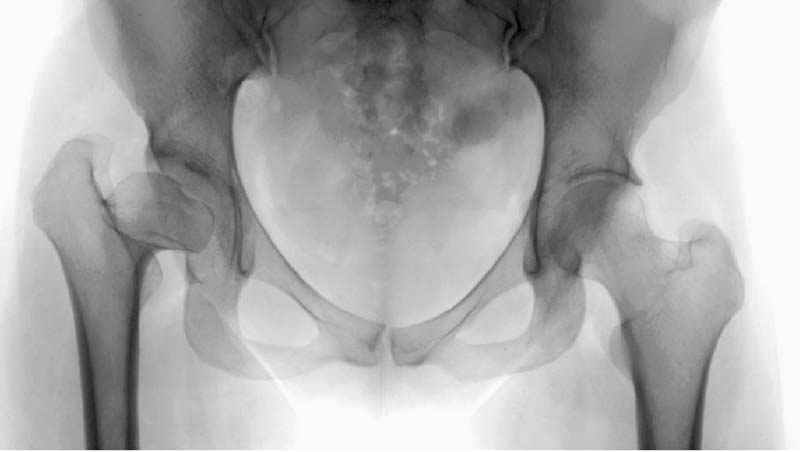

послеоперационные, с учетом биомеханики

сустава #11

отдаленный результат #12

№ 11-12 послеоперационные, с учетом биомеханики

сустава